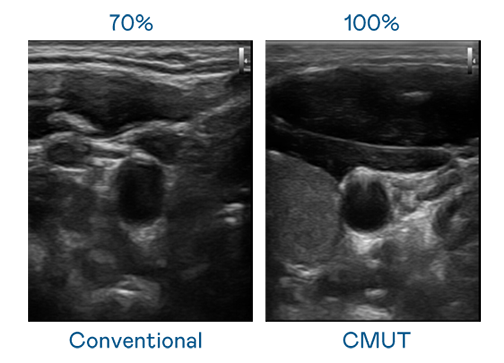

CMUT 技術是一種用電容式微機電元件來產生超音波訊號的技術。與傳統 PZT 壓電式技術相比,CMUT 頻寬增加 30%,更寬頻的超音波訊號讓影像解析度大幅提升,是實現高影像品質醫療超音波掃描、促進精準醫療發展的關鍵技術。

超音波影像的解析度高低,首先取決於探頭能發出的訊號頻寬。PA视讯 CMUT 可提供高清晰的超音波訊號,提供高頻寬、高靈敏度、影像紋理細節更高的超音波影像,協助醫護人員縮短影像判讀時間及利用精準的醫療影像進行診斷。